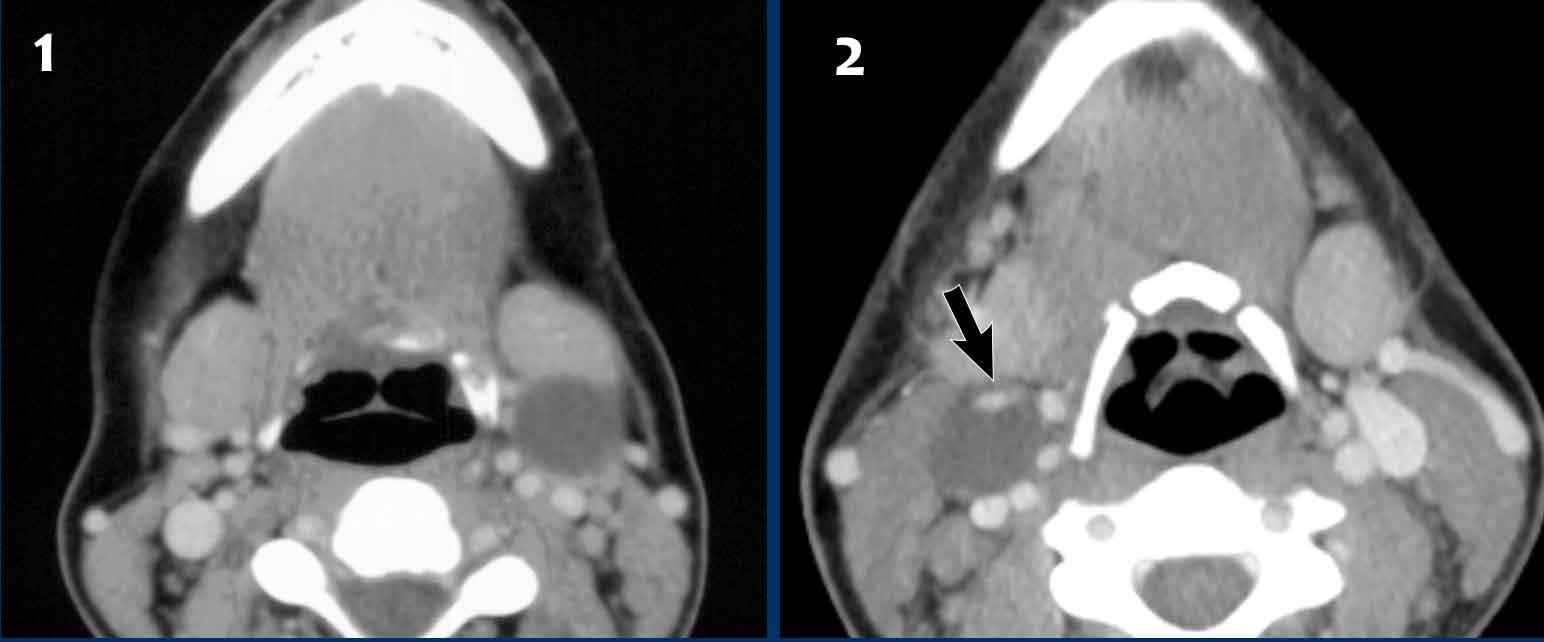

Các hình ảnh này thuộc về một nam bệnh nhân 69 tuổi với khối sưng vùng cổ trái.

Tổn thương được báo cáo là nang khe mang.

Mức dịch-dịch (đầu mũi tên) được cho là mảnh vụn do nhiễm trùng hoặc chảy máu trước đó.

Trong quá trình theo dõi, khối sưng tăng kích thước và mười tháng sau tổn thương được phẫu thuật cắt bỏ.

Kết quả giải phẫu bệnh: Di căn của ung thư biểu mô tế bào vảy, dương tính với dấu ấn P16.

Đây là dấu ấn chỉ điểm tình trạng dương tính với virus u nhú ở người (HPV).

Trong quá trình tìm kiếm khối u nguyên phát, bác sĩ chuyên khoa Tai Mũi Họng phát hiện amidan bên trái có kích thước hơi lớn hơn.

Lưu ý rằng vùng giảm tín hiệu trên bản đồ ADC nhỏ hơn vùng tăng tín hiệu trên DWI (b1000).

Điều này có nghĩa là chỉ có phần trung tâm của amidan là ung thư. Khối ung thư nằm sâu trong các hốc của amidan và thường không nhìn thấy được khi nội soi.

Sinh thiết xác nhận ung thư biểu mô tế bào vảy liên quan đến HPV và bệnh nhân được điều trị bằng xạ trị.

Dưới đây là hai trường hợp khác với các tổn thương (có vẻ) giống hệt nhau:

- Trường hợp này là nang khe mang (Case courtesy B.M. Verbist, Leiden)

- Trường hợp này là di căn hạch bạch huyết của ung thư tuyến giáp thể nhú.

Lưu ý hiện tượng ngấm thuốc dạng nốt ở thành nang (mũi tên).

Đặc điểm này không bao giờ thấy trong nang khe mang.